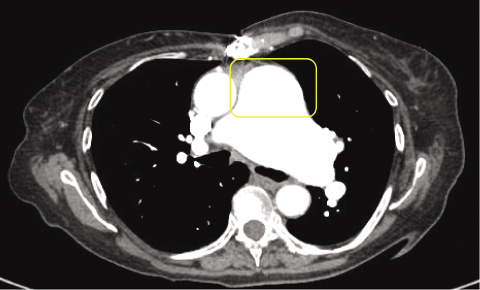

She opted for more conservative management and deferral of pulmonic valve replacement. Her beta blocker was replaced by a calcium channel blocker, and she was started on ambrisentan. She did relatively well for about one year after these changes, but then her symptoms worsened. Chest computed tomography (CT) revealed a slight increase in the size of her main pulmonary artery aneurysm (5.4 cm × 4.75 cm in coronal and 4.8 cm in axial images) with a stable left pulmonary artery aneurysm (Figure 2). Transthoracic echocardiogram (TTE) demonstrated an increase in RVSP compared to previous values (73 mmHg) as well as enlargement of the right atrium and ventricle. A repeat RHC was performed which revealed progression in her pulmonic valve gradient (22 mmHg). She underwent pulmonic valve replacement and had an uneventful post-operative course. She was slowly able to increase her physical activity and was walking over a mile in 30 minutes two months after her surgery, with further increases in distance and speed over the next year. She continued on her diuretics and calcium channel blocker, but ambrisentan was discontinued. Her pulmonary artery aneurysm is monitored yearly with a chest x-ray.

Figure 2

Figure 2. CT Chest axial view reveals a significantly enlarged main pulmonary artery (4.8 cm) as highlighted by the yellow rectangle.